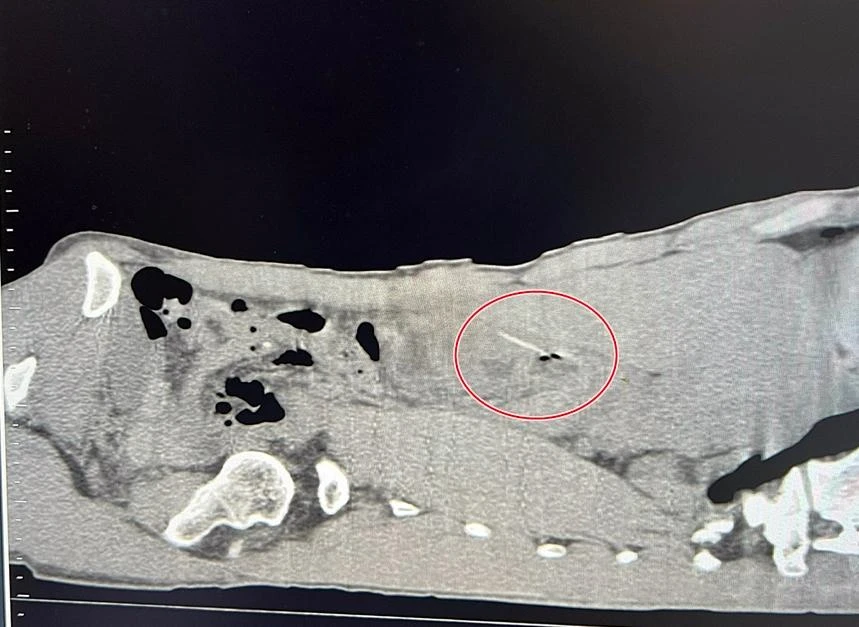

Các bác sĩ ở khoa Ngoại tổng hợp đã xử trí lấy dị vật ra và khâu lỗ thủng qua nội soi.

Dị vật được các bác sĩ lấy ra. |